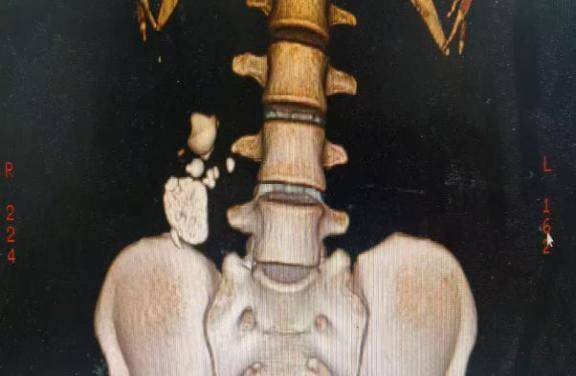

30岁的闵女士(化名)因右边反复腰疼得厉害到长沙泰和医院就诊,经检查发现,她的右肾里竟然藏着好几颗结石,最大的超过3.5厘米,有的还卡在肾盏里,属于复杂的“右肾铸型结石”。

(术前三维重建影像图)

术前,医生团队通过高清CT三维重建,就像看地图一样把闵女士肾里的结石位置、大小、分布摸得清清楚楚,特别是那些藏在肾下盏“死角”的结石。此外,三维模型还规划出了手术时最安全的穿刺路径,完美避开了血管密集区。